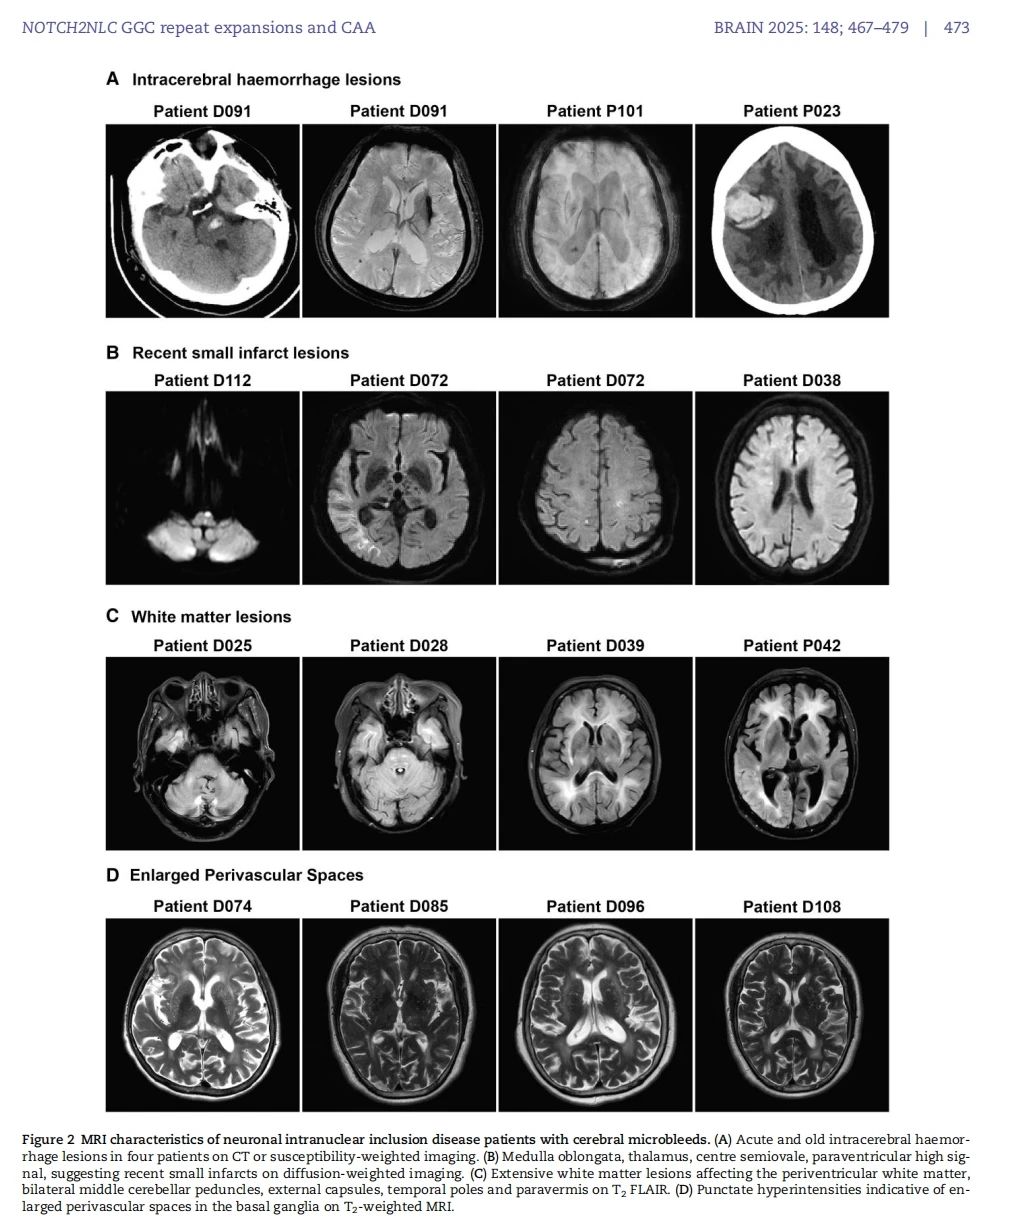

该研究成果显示,NOTCH2NLC 基因 GGC 重复扩增会使其翻译出富含甘氨酸

的蛋白质 uN2CpolyG。这种蛋白质不仅会在神经元内聚集形成包涵体,还能沉积在血管壁形成淀粉样物质,导致患者出现进行性认知功能障碍、多发脑微出血、反复皮层下梗死、关键脑区白质病变(外囊、颞极)、脑叶出血等症状。这一发现有助于解释神经元核内包涵体病患者特有的一些临床表现,像卒中样发作、癫痫

发作、偏头痛

发作、脑炎样发作等,这些症状实际上可能是由脑血管淀粉样变引起的短暂性局灶性神经系统发作(TFNE),即 “淀粉样发作(amyloid spells)”。